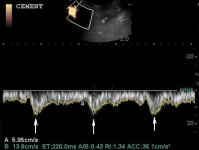

A New 464 Page Textbook, in Full-Color with 630 Pictures and Drawings, by Pete Ramey

A Few Pictures from the book:

Photos referenced in text from Bidwell/Bowker, Bowker, Clayton, Cowles, Hampson, Kellon, Ramey, Ridgway, Sullivan, Taylor, Watts.